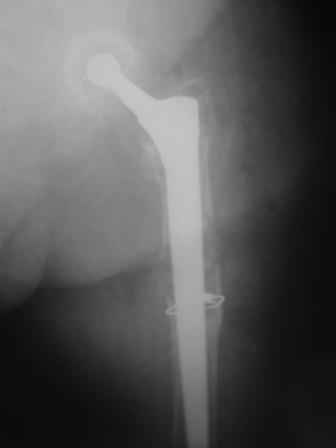

Female, rheumatoid, THA in 2003, car accident in 2006, failed plating. Nailing in Oct 2007. The nail is solid with hollow proximal part where the stem is docked. Last images are in 1 year after

nailing.

Reminded me of a case I did a couple years ago - 30 year old woman with juvenile rheumatoid arthritis and a nonunion below her stem. Fixed with retrograde nail which docked with the stem and a lateral locking plate. Image attached. One of the companies should come up with a stem design and nail system that anticipates this need.